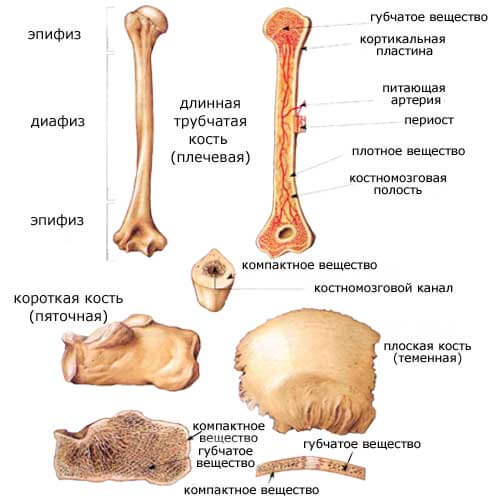

Изучение костного мозга: анатомия и функции

Раздел: Фотогалерея мыслей